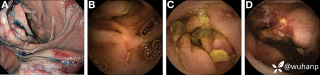

西地兰vip普外科医师

文/西地兰 特别声明:所有观点仅代表个人言论 特别声明:与当事双方均无利益相关 山东男孩,目前全网沸沸扬扬,看过一些观点,直言不讳地说,大多偏颇。要么一股脑地指责医方的全责,甚至有说千万别在县医院看病。要么又为医方无休止的遮羞,认为这样的手术在县医院做下来已经非常了不起。而我想到的是,以后面临类似的病例,我们怎么办?那么我们不如来一次专业的病案讨论。既然是事后讨论,难免有事后诸葛亮的感觉,但是假如下一次,同行们遭遇这样的病例,如何处置?这是医疗行业所面临的问题。希望我整理的这些思路和相关病例,对同行们有所帮助!就目前的资讯外界不足以判断是否需要急诊,如果需要急诊,那么只能根据术中所见进行处理,

目前知道的消息,第一,术前发现一个血肿,然后做增强CT发现一个占位,没说血肿与肿瘤的关系,术后病理没有描述肿瘤出现破裂出血,大概率就一个小血肿,我就不明白当地主任凭哪个指针去给这小孩开急诊刀的?哪个指南告诉他需要急诊开?第二,诊断不明确他想的不是进一步检查,一边观察一边进一步查,他反而选择腹腔镜探查,这个探查的指针在哪?第三,腹腔一个血肿,没有活动性出血,没有血压心率出现问题,为什么要开腹进去碰它?不能等血肿吸收再明确肿瘤性质吗?第四,1点进腹,3点病理结果出来,按这个时间还算顺利,应该还没出事,孩子还算平稳,病理是低度恶性,切了就治愈,他一年能开几台这手术,就敢继续做,拿孩子练手。第五,后面

2023年10月26日,来自山东菏泽市成武县的小烨和他家人的命运被彻底改变了。这个原本阳光、可爱的小男孩在一次意外被撞击后,在医院检查出了腹腔内存在肿瘤,并在手术中被切除了包括十二指肠、胰腺、大部分胃和小肠等多个器官。此后便无法再像正常人一样吃饭、喝水,活着要靠长期静脉注射营养液。一份2024年12月由第三方机构出具的司法鉴定意见书显示,当时给小烨做手术的成武县人民医院在该医疗行为中存在过错,与小烨的损害后果之间存在因果关系,建议医疗过错在损害后果中的原因力大小为同等原因。此外,另一份由成武县卫生健康局在2025年9月28日发出的书面答复中显示,成武县人民医院存在24小时内未完成病历;手术知情